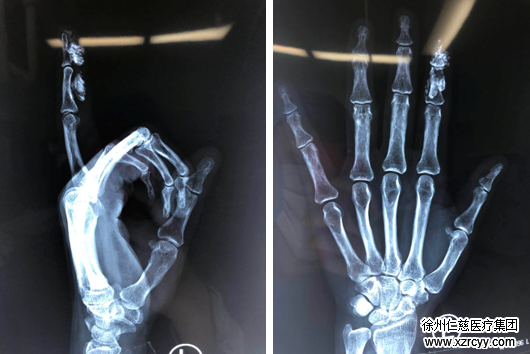

到了夜间,刘女士左示指胀痛持续加重,难以忍受,于是直奔必威官方首页官网betway就诊。经医生检查发现,刘女士左示指肿胀严重,远节指体已出现血供障碍。左手示指X线片检查见左示指中远节大量异物。

左示指X线片检查见:左示指中远节大量乳胶漆异物。